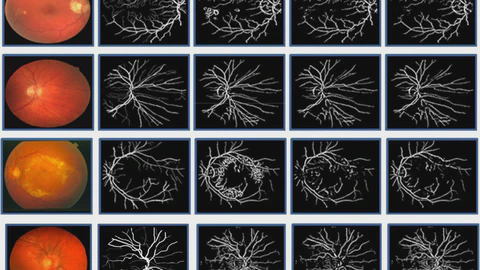

Before embarking on his Ph.D. journey, Sayed was a Lecturer in the Department of Computer Science and Engineering at The Millennium University, Bangladesh. He earned his Bachelor’s degree in Computer Science and Engineering from Khulna University, Bangladesh, in January 2019. His undergraduate thesis explored an automated method to segment retinal blood vessels from color fundus photographs, showcasing his early dedication to impactful research.

My research focuses on intelligent systems that perceive, predict, and adapt in dynamic environments, with applications spanning maritime security, simulation and medical imaging. I began my work in medical image analysis, developing machine learning, deep learning and graph-based methods for retinal vessel segmentation and breast cancer detection. These projects sparked my interest in computer vision and AI for supporting critical, human-centered decision-making. As a Ph.D. student at the University of Nevada, Reno, I currently focus on maritime intent recognition and threat prediction, developing frameworks that can be deployed to ships and algorithms that combine HMMs, LSTMs, and transformers to model vessel behavior in uncertain and adversarial environments. My work has led to multiple publications in top IEEE conferences and journals and international presentations.